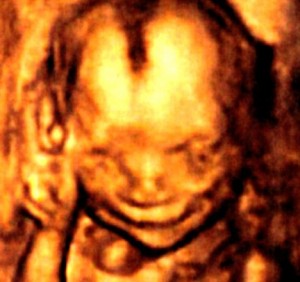

เผยภาพใบหน้า ทารกแสยะยิ้มในครรภ์ หลังคลอด

by lollipop888